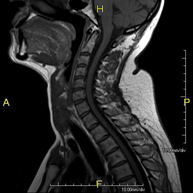

- RM Columna Cervical

Prueba diagnóstica no invasiva que consiste en la obtención de imágenes de alta definición anatómica de la columna cervical mediante el empleo de un campo electromagnético y ondas de radio (con un emisor y un receptor). No utiliza radiación ionizante. Indicaciones: traumatismo, degeneración de la columna, hernias.